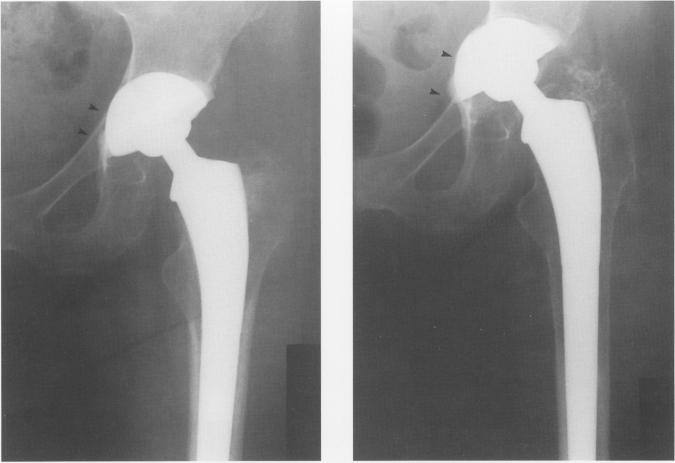

无骨水泥型马洛里-黑德初次全髋关节置换术的结果:5至7年的回顾

Results of the cementless Mallory-Head primary total hip arthroplasty: a 5 to 7 year review.

We reviewed the results of 172 plasma-sprayed, titanium primary total hip arthroplasties inserted without cement and followed 5 to 7 years. Hips were replaced for a wide range of diagnoses and patient ages. No femoral components had been revised nor were any considered unstable. Clinical results have been excellent; 88% of hips had either no or slight amount of pain and only 5% of patients had thigh pain when specifically asked. Radiographically, this femoral component achieved stability after an initial subsidence in 9% of cases. Extensive femoral bone resorption was rare, and distal cortical hypertrophy was commonly seen. Pelvic osteolysis occurred in 16 (9%) cases and was considered major in 10 of these. It was the cause of failure of 3 acetabular components. Femoral endosteal lysis was not observed. We concluded that mechanical stability of the Mallory-Head titanium total hip prostheses is excellent. However, significant pelvic osteolysis had occurred commonly with this implant design, and will continue to pose major reconstructive problems in the future.

摘要